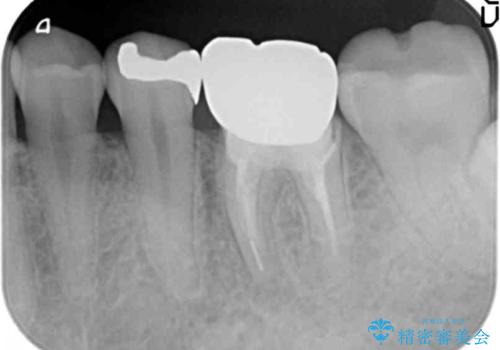

銀歯に限らず神経を除去する根管治療を行なった歯は、痛みが出ないまま虫歯が進行していることもしばしばみられます。

外から見ても状況は全くわからないことが多いため、X線による定期的な検査が重要です。